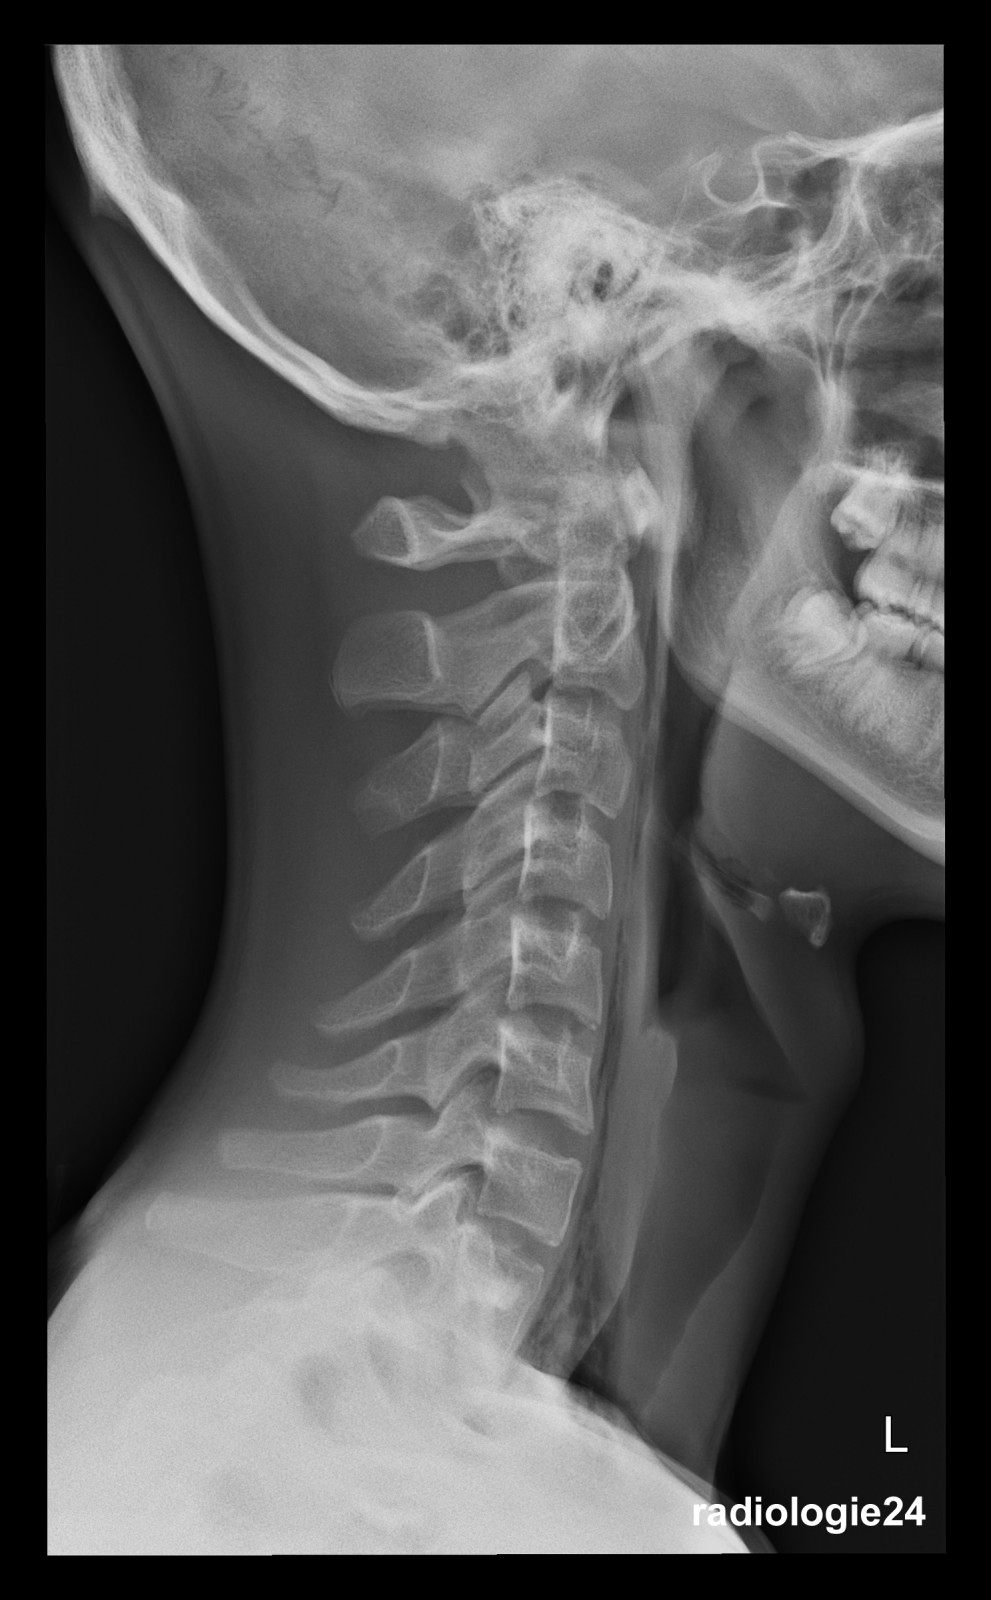

Röntgenfall des Monats Januar 2018 mit Auflösung

17 jähriger Patient Sturz auf den Rücken beim Crossbiken. Schmerzen HWS und Thorax. Fraktur, Pneumothorax, andere Pathologien? Weitere bildgebende Diagnostik? Welche? Warum?

Bild vergrössern

Link zur Auflösung mit ausführlichem Befund:

https://www.radiologie24.ch/radiologie-mediathek/roentgenfall_des_monats